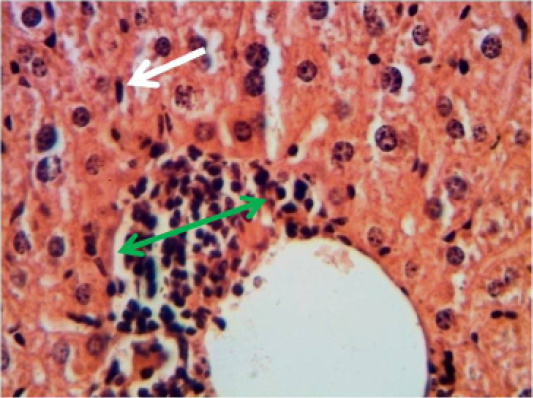

Histopathological section in the liver of animal feeding B-glucan shows mononuclear cells aggregation in portal area around proliferation of bile duct and portal blood vessels white arrow (H and E stain 40X)

Histopathological section in the liver of of animal feeding B-glucanshows mononuclear cells aggregation in one side of dilated central veins green arrow with proliferation of kupffer cells white arrow )H and E stain 40X)